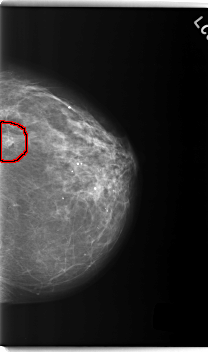

C_0218_1.LEFT_CC

LEFT_CC LINES 5976 PIXELS_PER_LINE 3528 BITS_PER_PIXEL 12 RESOLUTION 50 OVERLAY

FILE: C_0218_1.LEFT_CC.OVERLAY

TOTAL_ABNORMALITIES 1

ABNORMALITY 1

LESION_TYPE MASS SHAPE LOBULATED MARGINS ILL_DEFINED

ASSESSMENT 5

SUBTLETY 4

PATHOLOGY MALIGNANT

TOTAL_OUTLINES 1

BOUNDARY